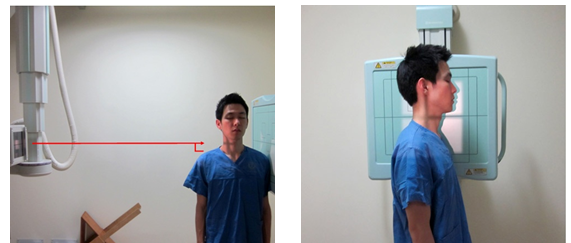

C-Spine Lateral

1. 목적

- Odontoid process, C2~C7의 body fracture, spinous process의 fracture, narrowing of disc space, C1의 anterior and posterior arch의 fracture를 관찰한다.

- spine의 정열이 바른지 본다.

2. 검사법

1) 환자자세

① 환자를 true lateral로 세우고 턱을 약간 들고 어깨의 힘을 빼도록 한다.

② C4 (adam’s apple)를 향해 수직 입사한다.

2) 호흡법 : 움직임이 없도록 숨을 멈춘 후 검사한다

5) 촬영 거리 : SID는 180cm으로 촬영한다.

6) 영상 결과